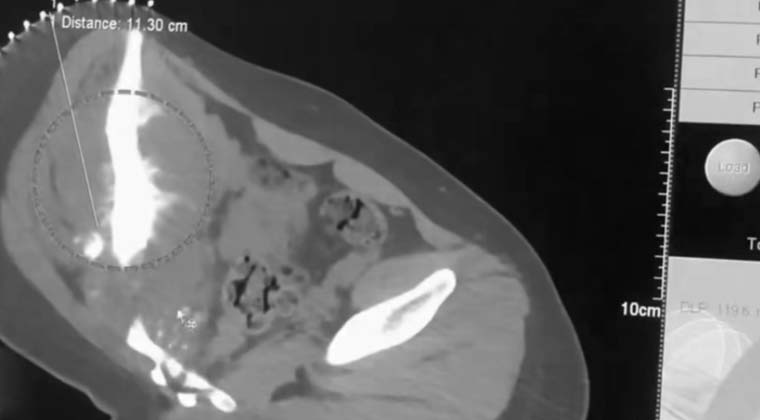

① Случай 1:

Пациентка: 17 лет, остеосаркома; пол: женский

Жалобы и течение болезни: во второй половине 2024 года пациентка почувствовала тянущие ощущения и отёк в правой нижней конечности. Дальнейшее обследование подтвердило остеосаркому. Очаг оказывал давление на область сустава, что влияло на ходьбу. Пациентка и её семья категорически отказались от хирургического удаления, подчеркнув желание максимально сохранить функцию конечности и искать малоинвазивное лечение с минимальной травмой.

Лечение и результат: после госпитализации пациентка прошла мультидисциплинарную оценку и получила криоабляцию. После лечения объём очага уменьшился по сравнению с исходным, симптомы снизились, созданы более благоприятные условия для последующего комплексного лечения и дальнейшего ведения.

(Область очага)

(«Ледяной шар», создаваемый криоабляционным зондом во время процедуры)

(Некроз опухолевой ткани)